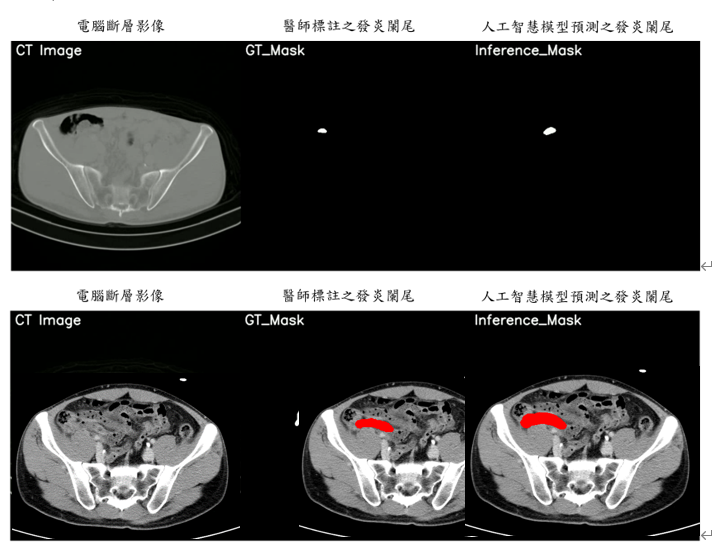

元智電機系攜手亞東影像醫學科團隊,使用電腦斷層掃描影像,進行判別是否發生急性闌尾炎。圖/元智大學提供

陳敦裕率領實驗室團隊,透過結合二維及三維人工智慧影像分割模型區分是否有急性闌尾炎,預測急性闌尾炎是否是特定急性腹痛原因,同時突顯CT掃描中的關鍵切片,以協助醫療專業人員快速檢測發炎的闌尾。